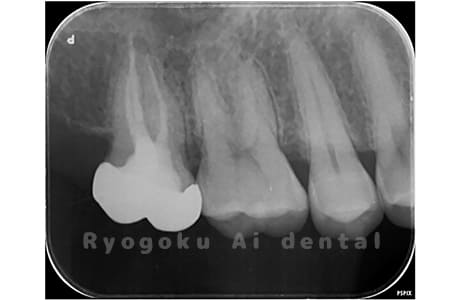

Case05

-

- 原因

- 慢性根尖性歯周炎

- 治療内容

- マイクロエンド

- 治療費用

- 121,000円(被せ物は含まない)

他院ではお薬の交換と抗生剤の処方で経過を診ていた患者さんです。歯茎の腫れが治らないとのことで、根管治療を開始し、2回目のご来院で腫れが引いたケースです。現在は被せ物も入り、良好に経過しております。

<リスク・副作用>

術後は痛み、腫れ、痺れなどの副作用が生じる場合があります。症状が再発する可能性があります。